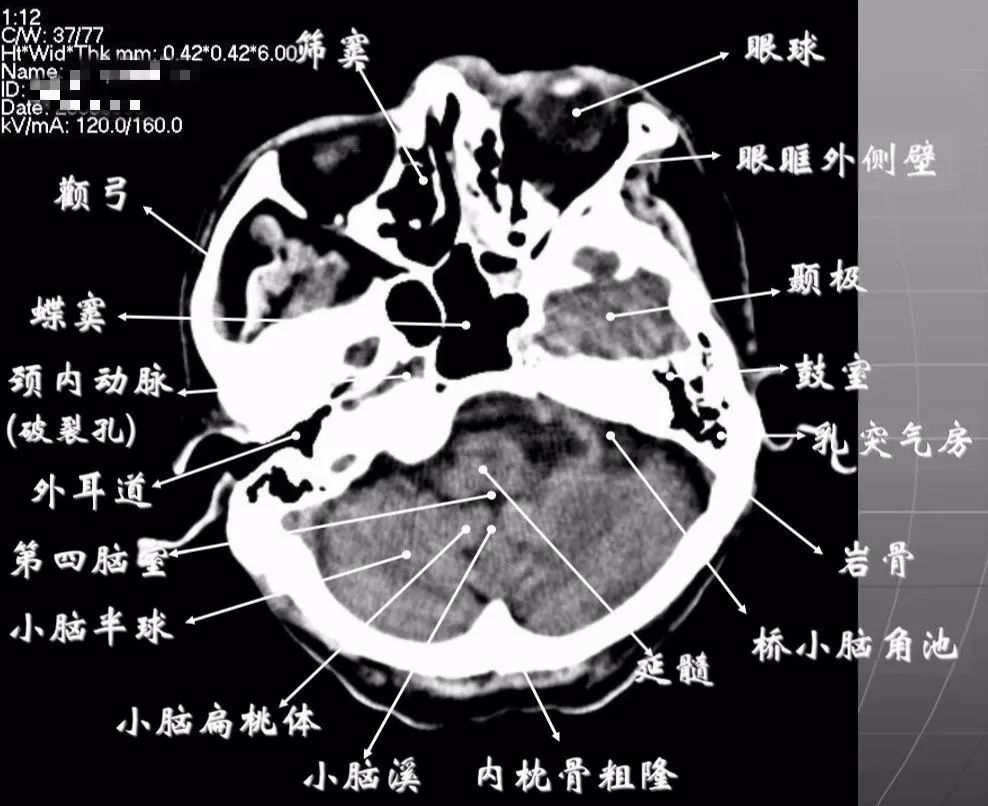

1、颅底层面眦耳线层面

颅前窝底部:眼眶、眼球、筛窦、蝶窦、前床突等。

颅中窝:前界——蝶骨;后界——颞骨岩部(岩骨);内缘——海绵窦及垂体窝;外缘——颞骨,窝内为颞叶,其内侧为海马回。

颅后窝:前缘——岩骨;后缘——枕骨;鞍背后方——脑桥前池,向两侧延伸为脑桥小脑角池。

第四脑室:位于颅后窝中线上,后面紧邻小脑蚓部,其两侧为小脑扁桃体。

延髓、脑桥:位于第四脑室前。